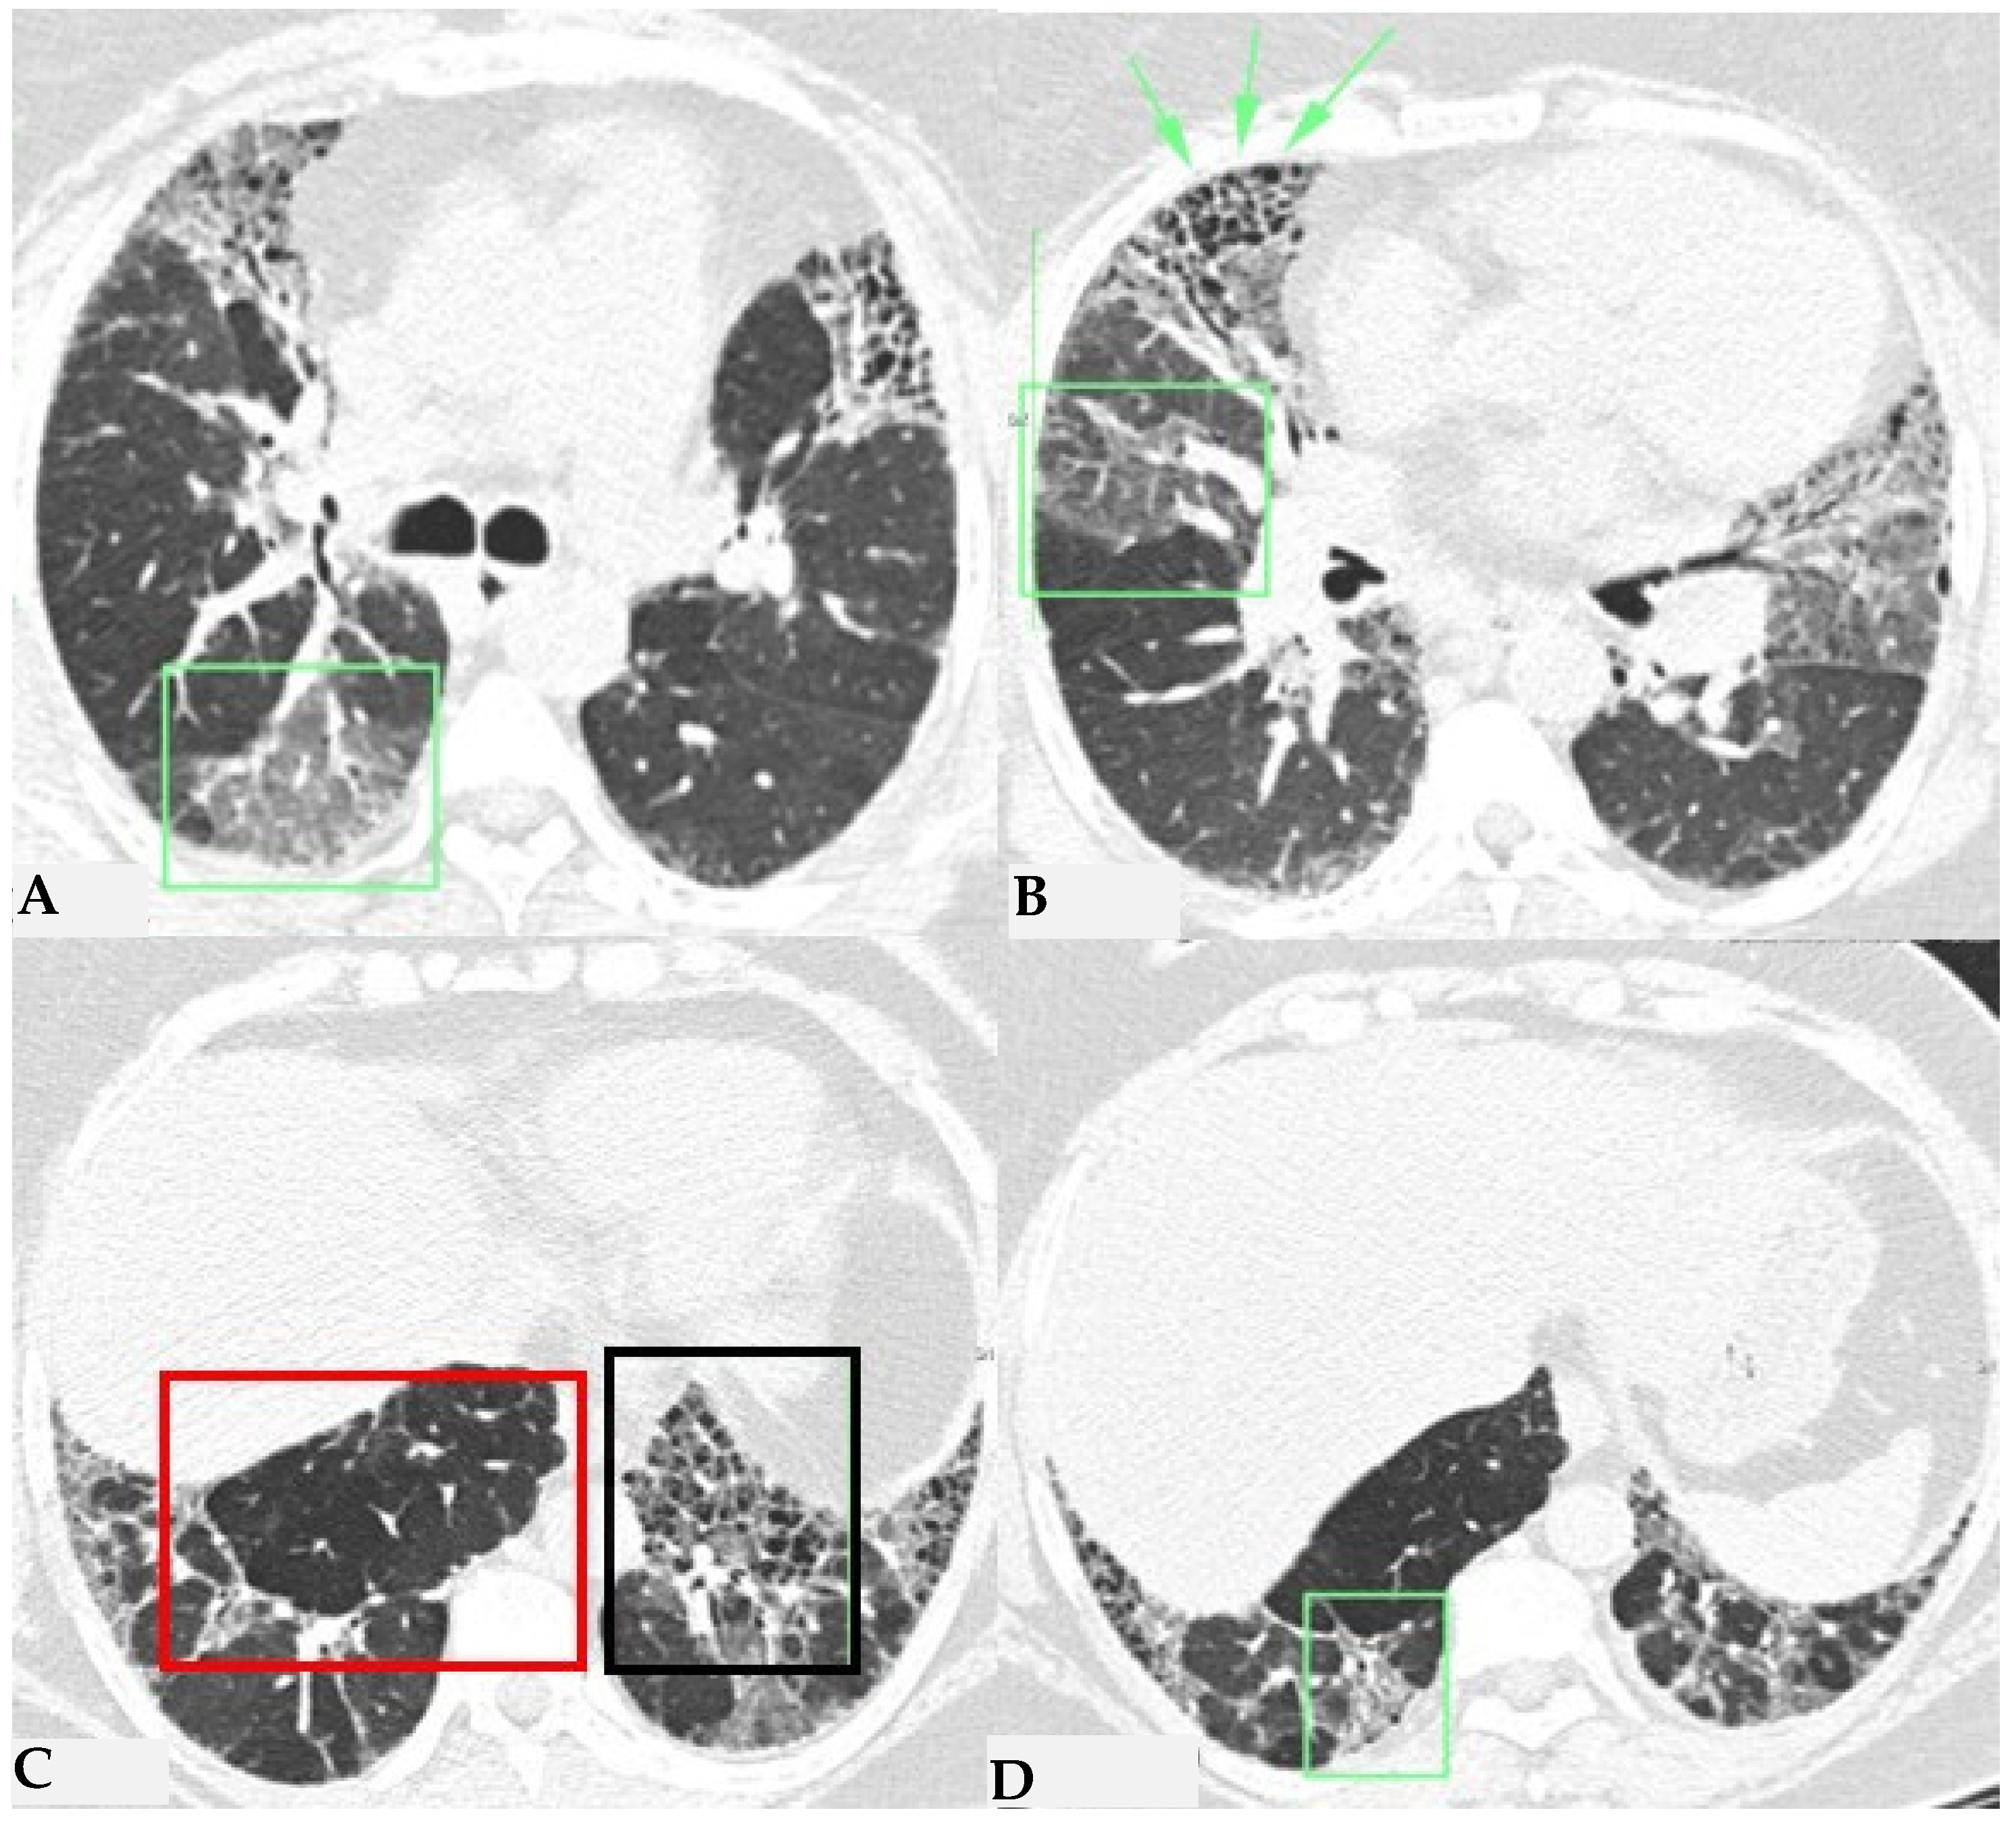

Ancillary findings such as smooth septal thickening and/or pleural effusion may also coexist with typical findings. The presence of numerous inflamed lymph nodes is often described. Another typical finding in the past described as the “head cheese pattern”, now described as “the three-density pattern”, was correlated with the combination of GGO opacities, integrated into a context of air trapping and normal lung. The clear lung heterogeneity, sometimes definitively recognizable in HRCT evaluations, is very suggestive and sometimes pathognomonic of HP in multiplanar reconstructions (Figure 2). Radiological features of HP are influenced by the histopathological stage of the disease at the time of diagnosis. According to international guidelines about HRCT features, HP (both the fibrotic and non-fibrotic forms) can be classified into “Typical HP”, “Compatible with HP” and “Indeterminate for HP”, each presenting typical, compatible or “not-specific” radiological and pathological elements, respectively. HRCT is a pivotal examination for diagnostic confirmation after a comprehensive clinical assessment, functional tests and BAL, with or without transbronchial biopsy (if deemed necessary by the clinician). It is also essential for the ongoing diagnostic process in the follow-up of patients with confirmed diagnoses through a MDT approach, providing information on therapeutic response and defining the possible progression of damage toward fibrotic transition as additional prognostic information useful for evaluating a different therapeutic approach (antifibrotic therapy). The distinctive feature of fibrotic HP is the coexistence of pulmonary fibrosis, often with signs of bronchial obstruction. In fibrotic HP, fibrosis more frequently appears as irregular and coarse reticulation associated with architectural distortion and septal thickening, which may be accompanied by bronchiectasis and bronchioloectasis that is more evident in ground-glass areas (Figure 3), with a centrifugal distribution (broncho-centric) and extension along the bronchovascular axis. These semiotic characteristics significantly differ from the fine and delicate reticulation observed in IPF, reflecting the intrinsic characteristics of immune-mediated inflammatory damage [7,8].

FHP: chest HRCT (A–D). Upper lobes and right lower lobe are characterized by areas of increased GGO density (green box: (A,D)) within which well-defined bronchiectasis and traction bronchiolectasis, indicative of established fibrotic damage, are observed (green arrows: (B)). Lower lobes extensively affected by mixed alterations, expressing damage to small airways with areas of reduced attenuation suggestive of air trapping (red box: (C)), and confirmed fibrotic damage with honeycombing and traction bronchiectasis (black box; (C)). Pattern of FHP.

The fibrotic damage in HP is often more severe and extensive in the middle or middle-lower lung zones, but at times, it can be equally distributed across all three lung zones with relative sparing of the subpleural compartment, presenting a “patchy” distribution as a trace of a previous inhalation-mediated immune attack. This distribution may not always exhibit a clear central or peripheral predominance, as evident in axial assessments or MPR reconstructions [7,8,9]. The obstruction of small airways, another significant and distinctive feature of HP, can manifest with various characteristics. In (NFHP), poorly defined centrilobular nodules (fluffy nodules) and mosaic attenuation can be observed. The corresponding HRCT semiotics in FHP presents a “three-density pattern” (Figure 5), characterized by the simultaneous presence of pulmonary lobules with normal density, lobules with (GGO) and lobules with reduced density and size of vascular structures (mosaic attenuation/air trapping) due to air entrapment resulting from broncho-obstruction (Figure 6). The three-density pattern becomes more evident in expiratory HRCT scans due to the air entrapment resulting from the pathogenesis of bronchiole obstruction [4,10].

FHP: chest HRCT ((A,B): axial scan). Visible is the “three density pattern”, with areas of the lung with normal density spared from pathological changes (red box); areas of the lung with reduced density characterized by a paucity of vascular and bronchial structures (yellow box); areas of the lung with increased density showing reticulations, interstitial thickening and traction bronchiectasis (green box). Lung cyst (red arrow) and areas of smoking-related paraseptal emphysema and advanced destructive emphysema (ADE) (blue arrows) are also present.

HRCT of the chest and magnification areas of RLL and LUL in FHP. Three-density pattern with lobular areas of reduced attenuation in both lungs (magnification images), overlapping with areas of increased density where distinct fibrotic alterations are evident, characterized by intra- and inter-lobular thickening with traction bronchiectasis and bronchiolectasis (red box). In certain patients, the absence of typical HRCT fibrotic features leads to their classification as “pattern compatible with FHP”. Suggestive elements of this pattern are fibrosis with a mixed central and peripheral distribution (Figure 7) and the fibrotic pattern with basal predominance (Figure 8).